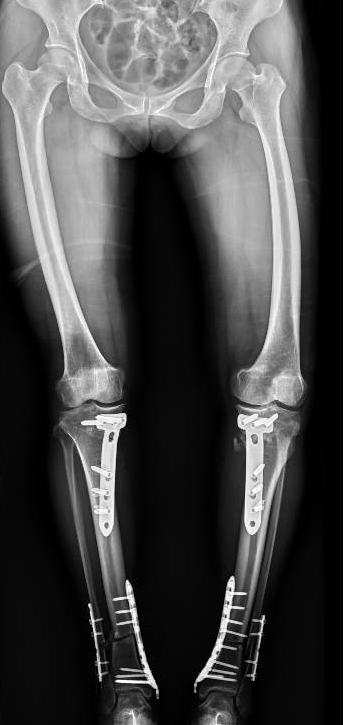

手术前 手术后

2024年8月13日,手术顺利进行。

手术很成功!经过精心的治疗和护理,董阿姨在9月顺利出院。当她再次站在镜前时,她惊喜地发现自己仿佛长高了一截,那份曾经让她备受折磨的疼痛与不适也逐渐消失了。